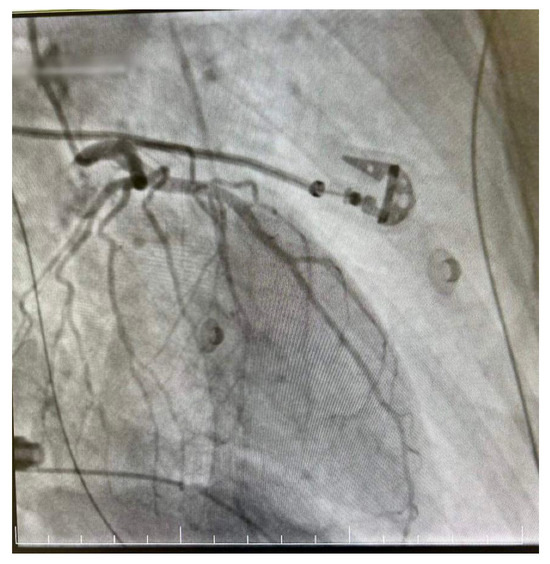

The decision was made to perform a coronarography, which showed no signs of acute or chronic coronary obstruction (Figure 5 and Figure 6). The patient was put on a continuous infusion of 0.01 micrograms/kg/min of noradrenaline and 1.8 mcg/kg/min of dobutamine with 40 mg of enoxaparin given the next day. She remained intubated for 48 h and the improvement of her hemodynamic status allowed the discontinuation of the inotropic medication the following day. After the steady improvement of the respiratory and cardiac functions, the patient’s clinical status allowed extubation with spontaneous breathing. The patient was started on the standard therapy for cardiac insufficiency, consisting of beta blockers, antiarrhythmic therapy, Angiotensin-converting enzyme (ACE) inhibitors and levosimendan. The following echocardiogram showed slow but steady improvement in the cardiac function. She was discharged from intensive care on day 6 and from the hospital on day 10. The echocardiogram conducted on the day she was discharged from the ICU revealed an EF of 25%, with akinesia of the ventricular apex and medio/apical segments, with no right ventricular dilatation and mild mitral regurgitation. On day 9 after HIPEC, the echocardiogram revealed an EF of 30–35% with hypokinesis of the apex and middle-to-apical segments of the heart. The patient did not complain of angina or dyspnea and tolerated lying in the supine position. She was discharged from the hospital on a combination of beta blockers, antiarrhythmic medication and ACE inhibitors, with a follow-up echocardiogram after one month.

Figure 5.

Right dominant coronary system without significant angiographic lesions.